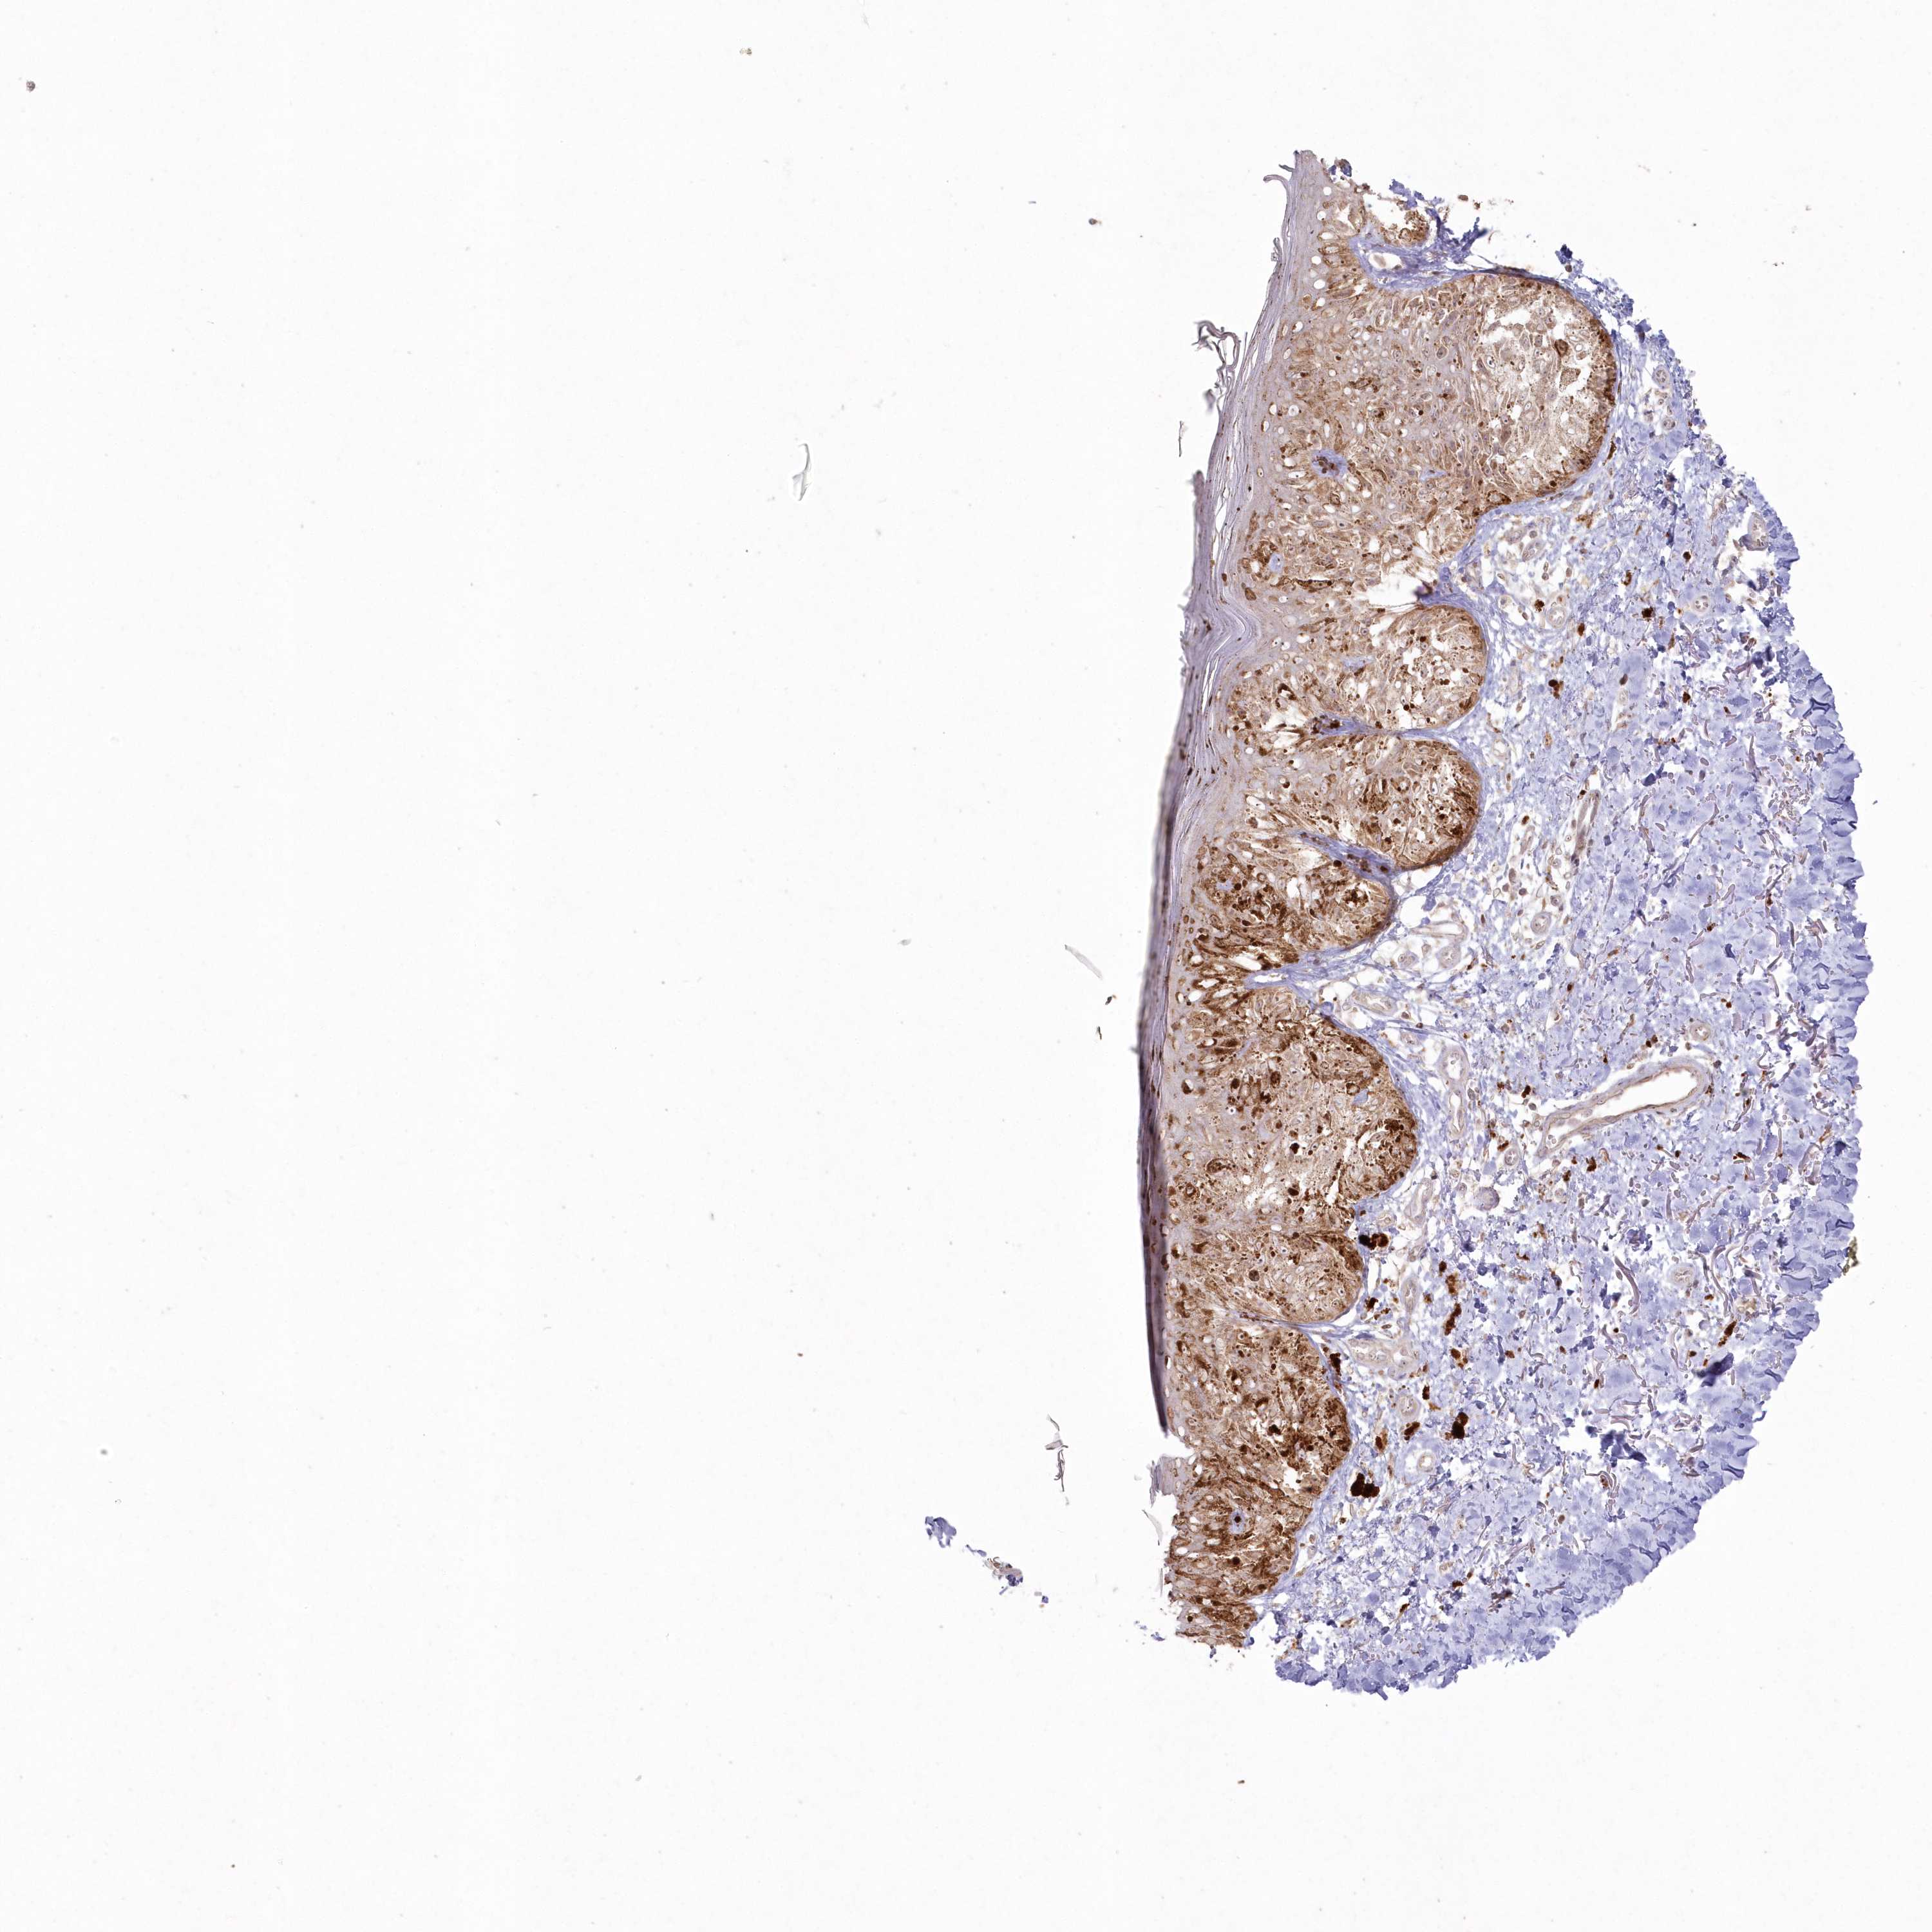

MELANOMA - Protein expressioni

A mouse-over function shows sample information and annotation data. Click on an image to view it in a full screen mode. Samples can be filtered based on level of antibody staining by selecting one or several of the following categories: high, medium, low and not detected. The assay and annotation is described here.

Note that samples used for immunohistochemistry by the Human Protein Atlas do not correspond to samples in the TCGA dataset.

Antibody stainingi

Antibody staining in the annotated cell types in the current human tissue is reported as not detected, low, medium, or high, based on conventional immunohistochemistry profiling in selected tissues. This score is based on the combination of the staining intensity and fraction of stained cells.

Each image is clickable and will lead to virtual microscopy that enables deeper exploration of all samples and also displays staining intensity scores, fraction scores and subcellular localization as well as patient and tissue information for each sample.

Antibody HPA037770

Antibody HPA037771

Staining

High

Medium

Low

Not detected

Intensity

Strong

Moderate

Weak

Negative

Quantity

>75%

75%-25%

<25%

None

Location

Nuclear

Cytoplasmic/membranous

Cytoplasmic/membranous,nuclear

Malignant melanoma, NOS

Malignant melanoma, Metastatic site